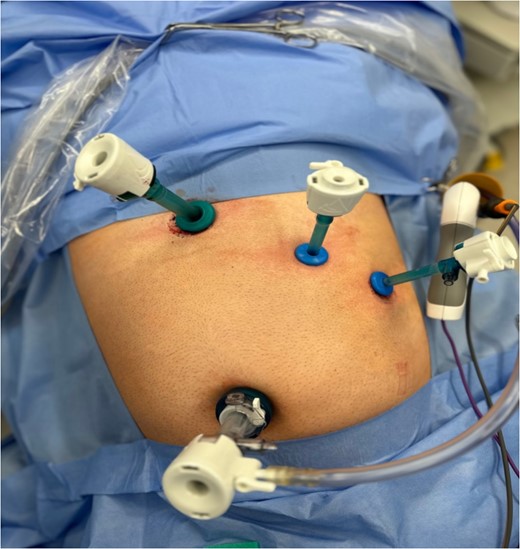

The patient was put under general anaesthesia and placed in the supine position. The operating surgeon and first assistant operating the camera stood on the patient’s right-hand side. The second assistant and scrub nurse stood opposite on the patient’s left. The laparoscopic stack and screen were positioned at the patient’s left shoulder. A 12 mm port was placed in the infra-umbilical position following open Hassan cut down, and pneumoperitoneum was achieved with CO2 at 14 mmHg and a flow rate of 5 LPM. One 11 mm port and two 5 mm ports were inserted under direct vision in an exact mirror image of a standard LC with normal anatomical positioning. This involved port placement as follows; 11 mm port in the subxiphoid area, 5 mm port in the left medial subcostal area, and a further 5 mm port in the left lateral subcostal area (Fig. 2). The patient was positioned with 30 degrees of head up and 20 degrees of left sided tilt. Upon insertion of the camera, it was imperative that we correctly orientated ourselves to the patient’s anatomy (Fig. 3).

Intra-operative image taken illustrating laparoscopic port setup.